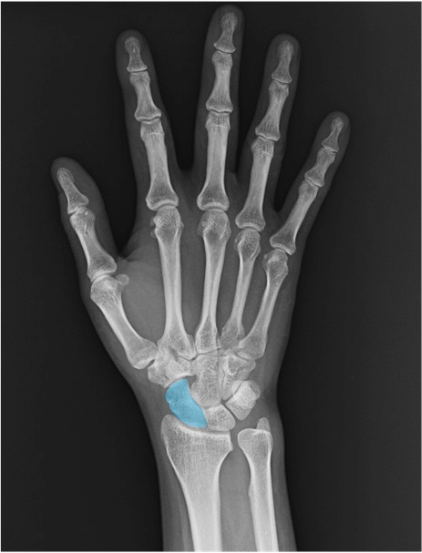

舟状骨(scaphoid)

近位列橈側。PA正面、尺屈位(ulnar deviation)で舟状骨の短縮・重なりを回避しやすく、腰部(waist)の評価がしやすくなります。